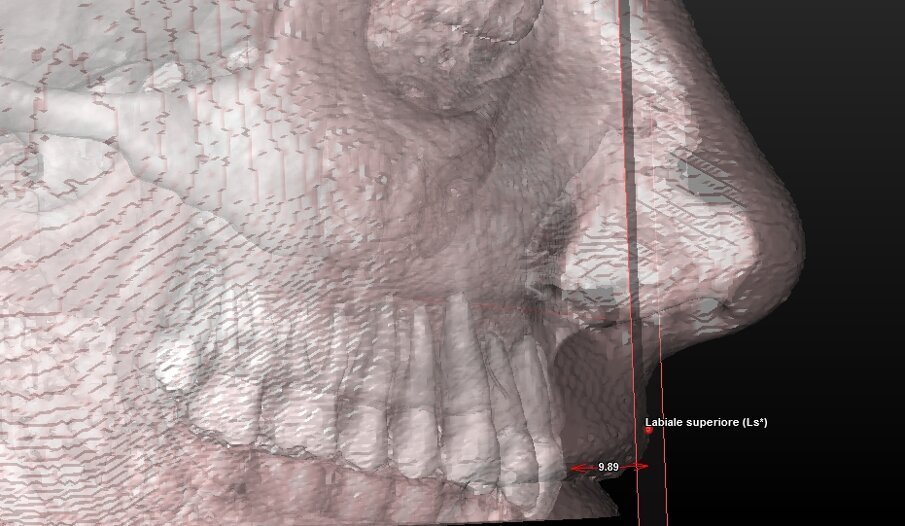

5 landmark per la valutazione estetica dei tessuti molli (Tab. 2) (Fig. 4).

| Sn (Subnasale) |

Punto mediano cutaneo d’incontro tra columella e labbro superiore. |

| Columella |

Punto mediano cutaneo più alto di columella a livello d’incontro tra le narici. |

Componente tessuto molle (Tab. 5) (Figg. 10a-11):

| Angolo Naso-Labiale |

gradi |

U 98,7- 114,1

F 96,7-110,3 |

Angolo tra i punti Columella-Subnasale-Labiale superiore |

Fig. 10a_Valutazione dei tessuti molli: angolo naso-labiale.